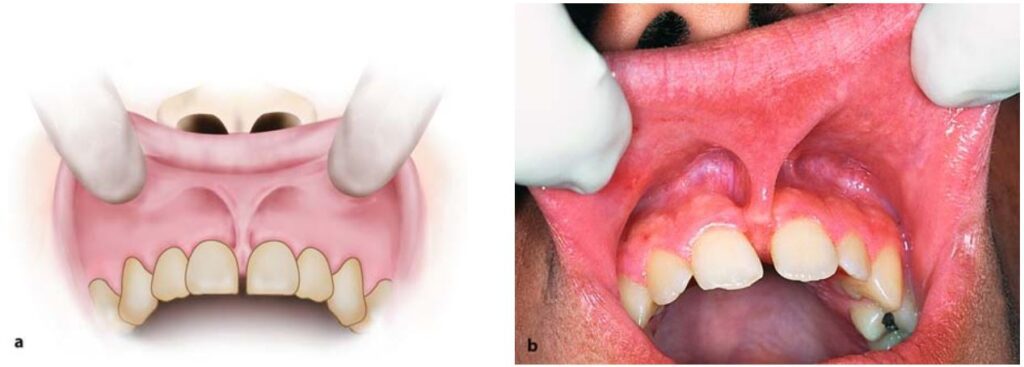

Trong nhiều trường hợp thực hiện hàm giả toàn bộ ở hàm trên hay điều trị chỉnh nha ở người trẻ đòi hỏi phải cắt bỏ thắng môi, má hoặc lưỡi nếu chúng gây cản trở (H10.72).

Cắt thắng môi hàm trên

Cắt thắng môi là thủ thuật đơn giản, thường dễ và các bác sĩ tổng quát hoàn toàn thực hiện được, với nhiều kĩ thuật khác nhau.

Kĩ thuật được áp dụng nhiều nhất là sử dụng 2 kẹp cầm máu.

Sau khi gây tê thì kéo môi trên lên, dùng 2 kẹp cầm máu cong để kẹp vào thắng môi, nhằm giữ cố định bờ trên và bờ dưới thắng (H10.74 và 10.75).